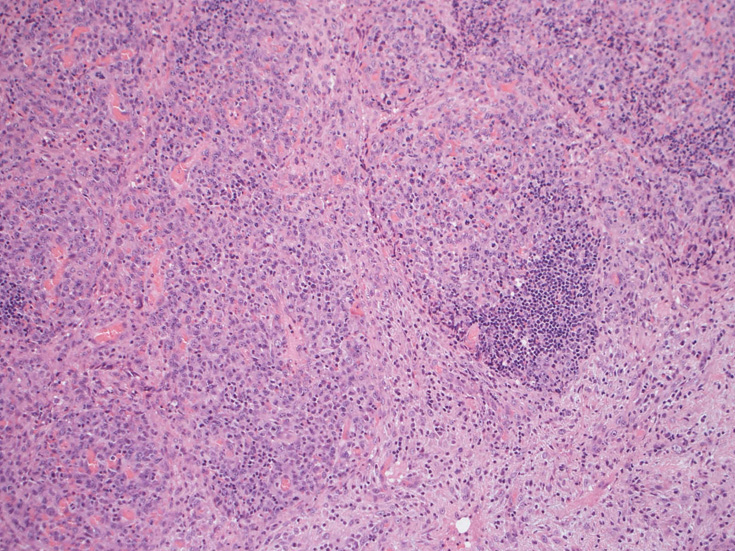

リンパ節, 増殖腫瘍細胞の病理所見

腹膜脂肪組織内から生検されたリンパ節は基本構造を失っている。低倍率のHE所見では異型細胞が不鮮明な結節構造を形成して増殖している。一次リンパ濾胞を腫瘍細胞が置換しているように見える所見がある。

高倍率x400では, 増殖細胞はcentroblastに似て複数の明瞭な核小体をもった淡明な大型類円ないし卵円形核を持っている。核分裂像が多い。この症例では多型はめだたない。典型的な腎臓型のくびれた核を持つ細胞などはない。ALKの形態的variant症例と考えられるが, 化学療法後の再発による影響も否定できない。